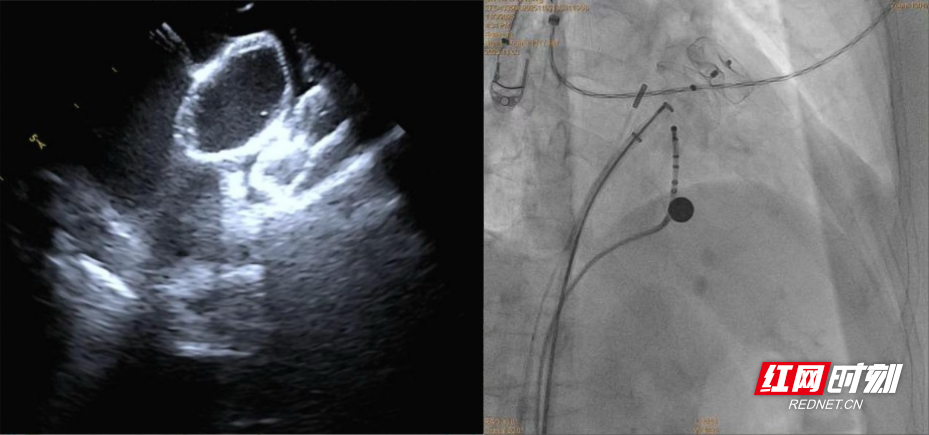

手术在导管室、麻醉科、超声科等多科室协作下进行。团队经股静脉穿刺,在三维标测系统引导下完成房颤射频消融,随后在X线及心腔内超声指导下植入左心耳封堵伞,成功闭合左心耳开口。整台手术历时约两小时,患者房颤转复为正常窦性心律,术后恢复良好,胸闷、心悸症状明显改善。